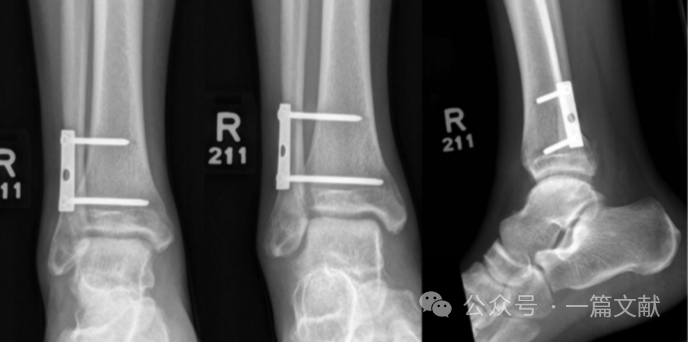

1,胫腓联合部螺钉过长影响复位,如下图:左图中钢板远端螺钉过长,进入胫腓联合,干扰复位。中间图为调整螺钉长度后重新复位,右侧图为最终固定后,位置满意。图片